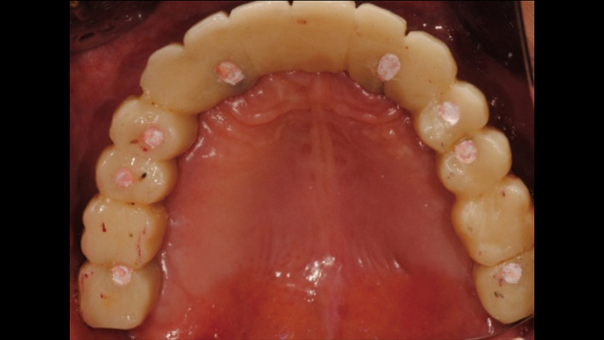

Clinical case: Advantage of fuse abutment with AnyRidge implant for immediate loading in

upper fully edentulous case

“AnyRidge shows excellent initial stability

& stable results after immediate loading in

upper fully edentulous case. ”

Clinical case: Extraction of all teeth in upper maxilla,

immediate implant placement, & provisionalization

- Courtesy of Dr. Iulian Filipov, Romania -